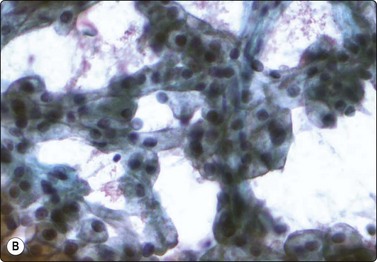

image

Fig. 12.28 Wilms’ tumor

Small round cell tumor pattern of undifferentiated blastema (A, MGG; B, Pap, HP).

Criteria for diagnosis

Numerous undifferentiated small cells, single and in tight clusters (blastema),

Small, round or ovoid, hyperchromatic nuclei; multiple small nucleoli,

Scanty cytoplasm,

Epithelial differentiation: rosettes, tubular structures or cords (commonly present),

Mesenchymal differentiation: spindle cells (sometimes present).

Wilms’ tumor (nephroblastoma) is predominantly a tumor of childhood and is dealt with in more detail in Chapter 17. However, it can also occur in adults. Smears are usually dominated by small, undifferentiated malignant cells representing blastema. A specific diagnosis requires in addition evidence of epithelial and mesenchymal differentiation, but this may only be obvious in the better-differentiated tumors. Individual cells generally appear undifferentiated. Epithelial differentiation is suggested by microarchitectural patterns such as rosettes, tubules or cords (Fig. 12.27), which are not always present in smears. Correlation with clinical and radiological findings is important. The diagnosis may be supported by ancillary studies. The results of immunostaining are variable, depending on differentiation. Useful markers are vimentin, LMWCK, EMA and WT1. Heterogeneous cytogenetic abnormalities can be demonstrated in a proportion of tumors.